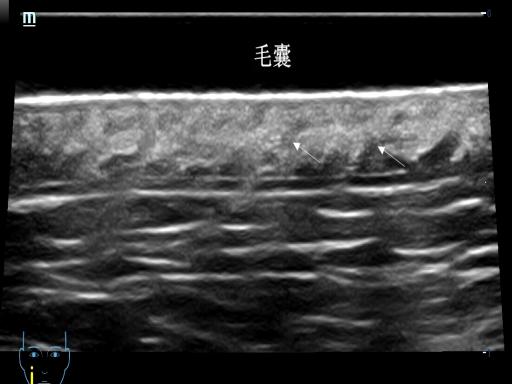

我们的皮肤从外到内分为表皮、真皮、皮下组织三层,就像一层薄外套裹着两层“保暖层”。在超高频探头下,薄薄的皮肤可以变成一张 “皮肤剖面图” ,不仅可以看到表皮、真皮、皮下组织的结构,精确测量其厚度,还可以清晰显示其内的毛发、毛囊、皮脂腺等肉眼及普通超声无法识别的结构。

脱发评估

超高频超声可以显示头皮毛囊密度及毛囊状态,正常人的毛囊密集、排列整齐,脂溢性脱发患者毛囊间距增宽,斑秃显示毛囊稀疏、排列杂乱。超高频超声可以为治疗选择、疗效评估及随访监测提供量化工具。